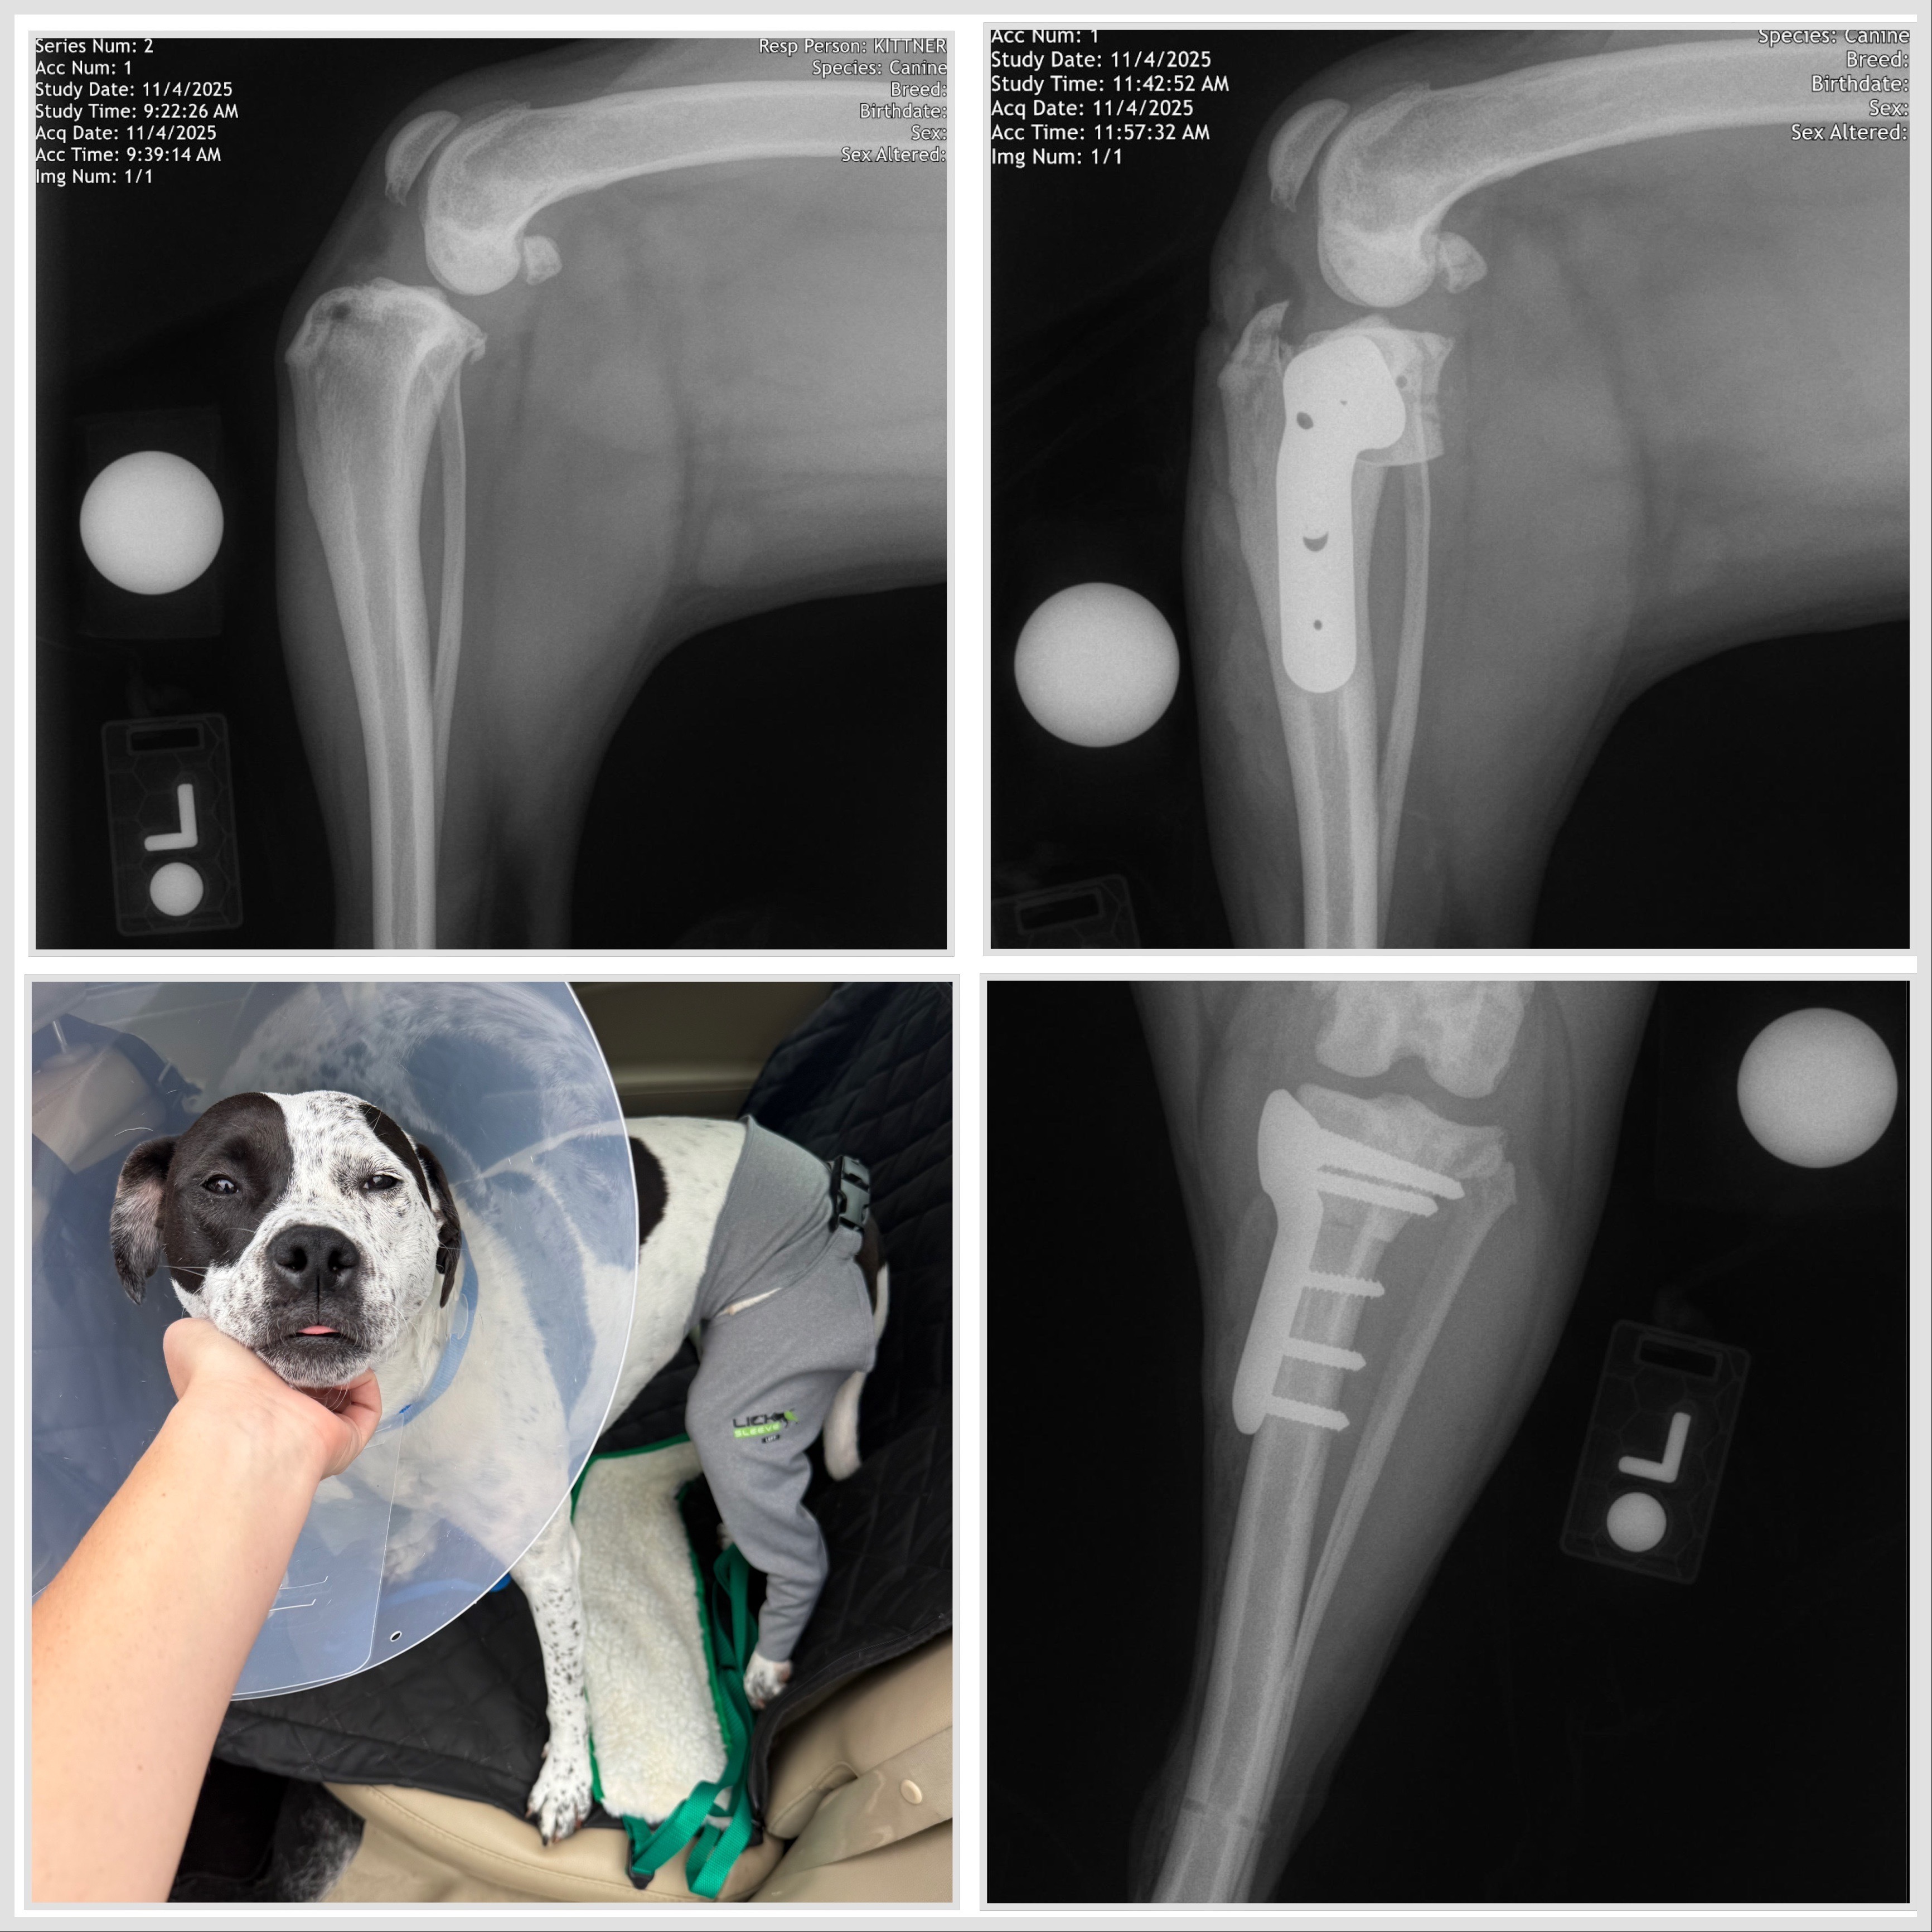

If you know Daisy, you know her as fearless, playful, and chaotic in the best way. She loves every person and animal she meets.

Unfortunately, Daisy recently tore her ACL and needed surgery so she wouldn’t lose the use of her leg. Thanks to pet insurance, I was able to get her the surgery she needed, but it only covered part of the cost. The remaining bills, along with the medications, follow-up care, and the enrichment toys she’ll need during her long recovery, have become more than I can manage on my own.

A lot of people care about Daisy, and I wanted to share this in case anyone would like to help. Even a small donation toward her medical expenses or recovery care would make a huge difference. Most importantly, it will help Daisy get back to running, playing, and being the happy little whirlwind everyone knows her to be.